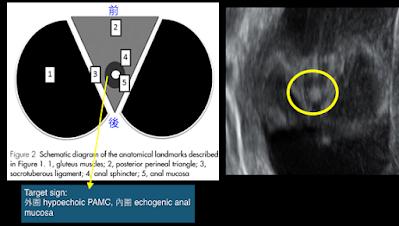

至於 direct findings 就是更直接的去看肛門周圍肌肉 (PAMC) 和肛門黏膜。肛門沒長好時 PAMC 勢必也沒長好,但這只限於 high atresia, 因為 low atresia 時 PAMC 是完好的。肌肉在超音波呈現低回音,產前可從coronal, sagittal 和 axial plane 下去找胎兒的 PAMC, 正常縱切面下(coronal, sagittal),在胎兒腸道末端到會陰部之間會看到兩道平行的 hypoechoic stripes; 橫切面 (axial) 則會看一圈 hypoechoic ring (圖2)就是 PAMC[6]。

圖2. PAMC (參考資料:Ultrasound Obstet Gynecol 2012; 39: 521–527)